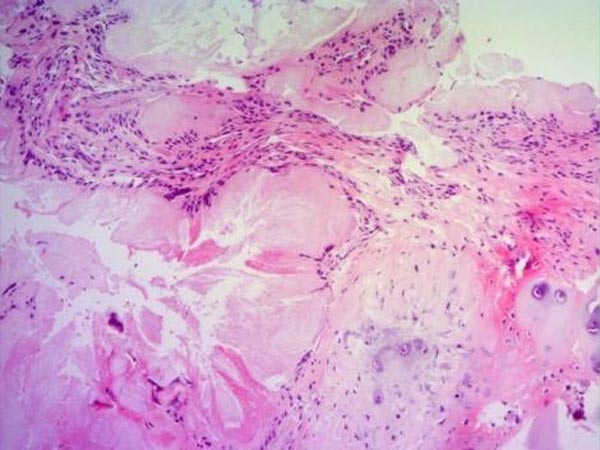

Kết quả giải phẫu bệnh: khối u là các tinh thể natri urate.

A: Hình ảnh khối màu trắng đặc quánh, ngoài màng cứng tủy, khu trú cung sau T1 bên phải và diện khớp T1-T2, thâm nhiễm vào tổ chức dây chằng vàng, gây hẹp ống sống và chèn ép tủy ngang mức. B. Hình ảnh các tinh thể natri urate lấy ra từ vị trí phẫu thuật.